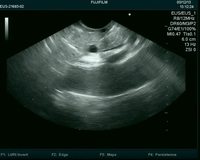

超声内镜引导下胆道引流术治疗恶性梗阻性黄疸

作者:陈萃 孙波 胡冰

2018-07-20

内镜超声引导下无水乙醇消融术治疗胰腺囊性肿瘤

作者:孙力祺 蒋斐 金震东

2018-04-23